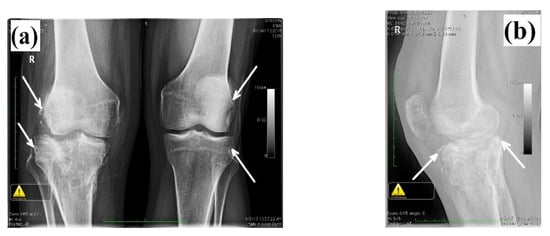

The present study was performed in agreement with the ethical standards of the Helsinki Declaration and approved by the Ethical Committee of University of Oradea, Romania (ref. nr. 08/05.2020); the patient signed an informed consent agreement for the surgical protocol. The patient was a 60-year-old male, admitted to the orthopedics clinic I at the Emergency County Hospital, Oradea (Romania) claiming right knee pain and partial functional impotence of the right pelvic limb. From the personal pathologic background of the patient, we noted that he was the victim of a car crush and suffered a fracture of the right tibial plateau, eight years before medical examination, for which surgery was performed. Additionally, the patient presented hydrostatic varices of the lower limbs bilaterally, lumbar spondylosis and lumbar discopathy. After clinical and paraclinical examination (radiological exam), the diagnosis was established: right gonarthrosis which appeared secondary to a tibial plateau fracture. Total cemented arthroplasty at the level of the right knee was performed using NexGen® complete knee solution (Zimmer, Warsaw, IN, USA) and Gentafix®1 (Teknimed, Vic en Bigorre, France) acrylic bone cement. The patient had a favorable evolution after surgery. After 10 years, a clinical and radiological reassessment was made; a destabilization of the tibial component was noticed. As a consequence, revision of the total knee arthroplasty was performed. During the surgery, it the instability of the tibial components accompanied by decementation and loosening was noticed. No sign of sepsis was found. The radiological examination before and after arthroplasty and revision surgery is presented in Figure 1.

Figure 1.

(a) Bilateral knee radiography—anteroposterior view, demonstrating advanced degenerative changes (gonarthrosis stadium IV) at the level of the right knee (white arrows), secondary to the malunion of tibial plateau fracture; (b) lateral view, showing depression of the lateral tibial plateau (white arrow); (c) anteroposterior and later view, eight years after surgery; both views highlight the loosening of the tibial component, minimal osteolysis of the medial tibial plateau (anteroposterior view) and minimal osteolysis around the distal region of the tibial implant (lateral view); (d) anteroposterior and lateral view after revision of the total knee arthroplasty using modular tibial implant with short stem and two screws for re-insertion of the patellar tendon (after tibial tuberosity osteotomy).